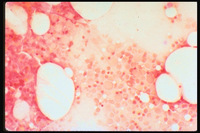

Prussian blue (iron) stained bone marrow

This image shows iron stains for comparison. In the left upper corner iron is increased,  as demonstrated by the large amount of blue material.  The next two images show decreasing amounts of iron.  The right bottom image shows no iron.  This test is considered the gold standard for evaluating marrow iron stores.

Also included is a Prussian blue (iron) stained bone marrow.  This low power view of an iron stained bone marrow shows no stainable iron.  Iron is manifest by blue colorations and granules, absent in this example.